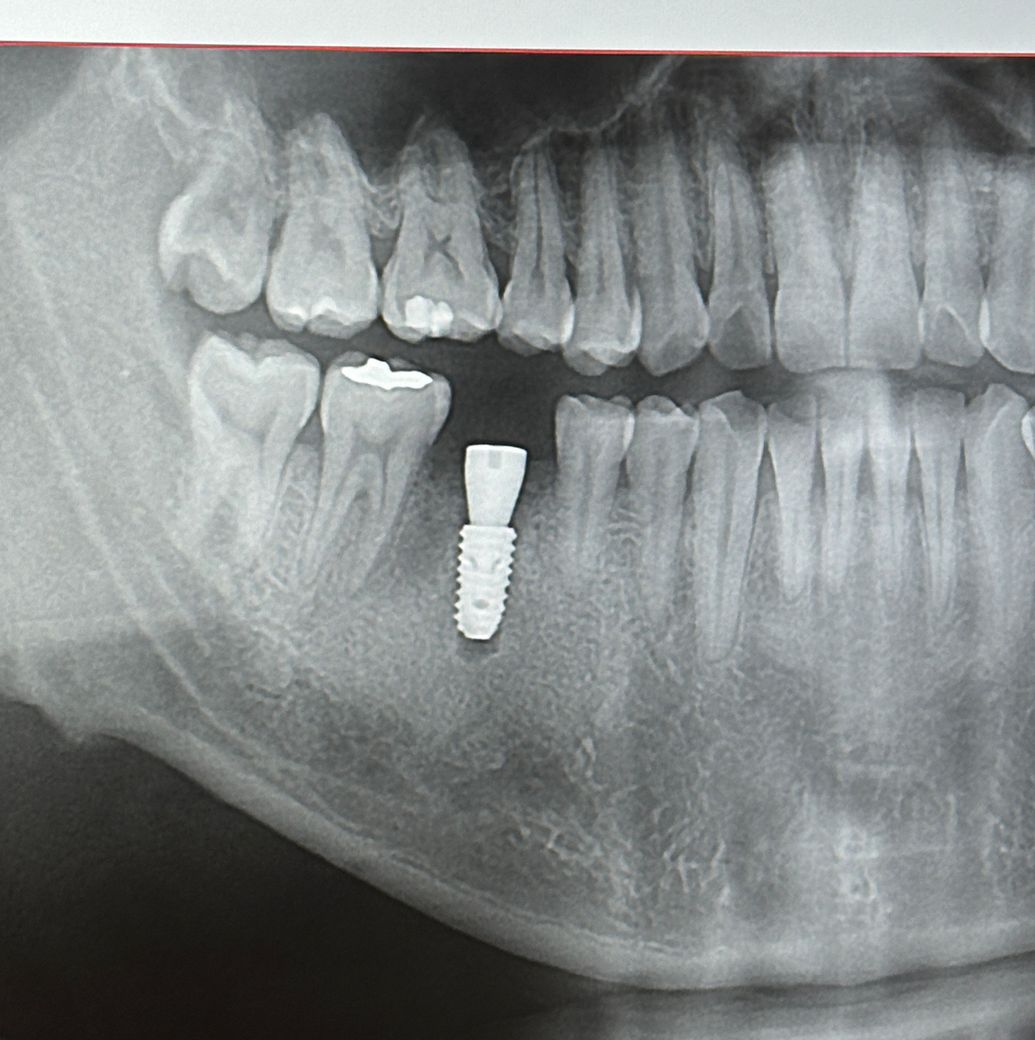

오늘 임플란트 수술+뼈이식 받았는데요

잘된걸까요? 다음3달이후에는 다시 수술할필요가앖이 바로 머리올린다고 하시네요

1. 임플란트 뿌리를 심은 후(1차 수술)에 임플란트 뿌리가 뼈에 붙을 때까지 뚜껑을 닫아두는데 두 종류가 있습니다. 그 중에 2차 수술을 진행하지 않아도 되는 타입(힐링 어버트먼트)을 달아둔 상태입니다. 3달 후 다시 수술할 필요가 없다는 것은 그걸 의미하고요.